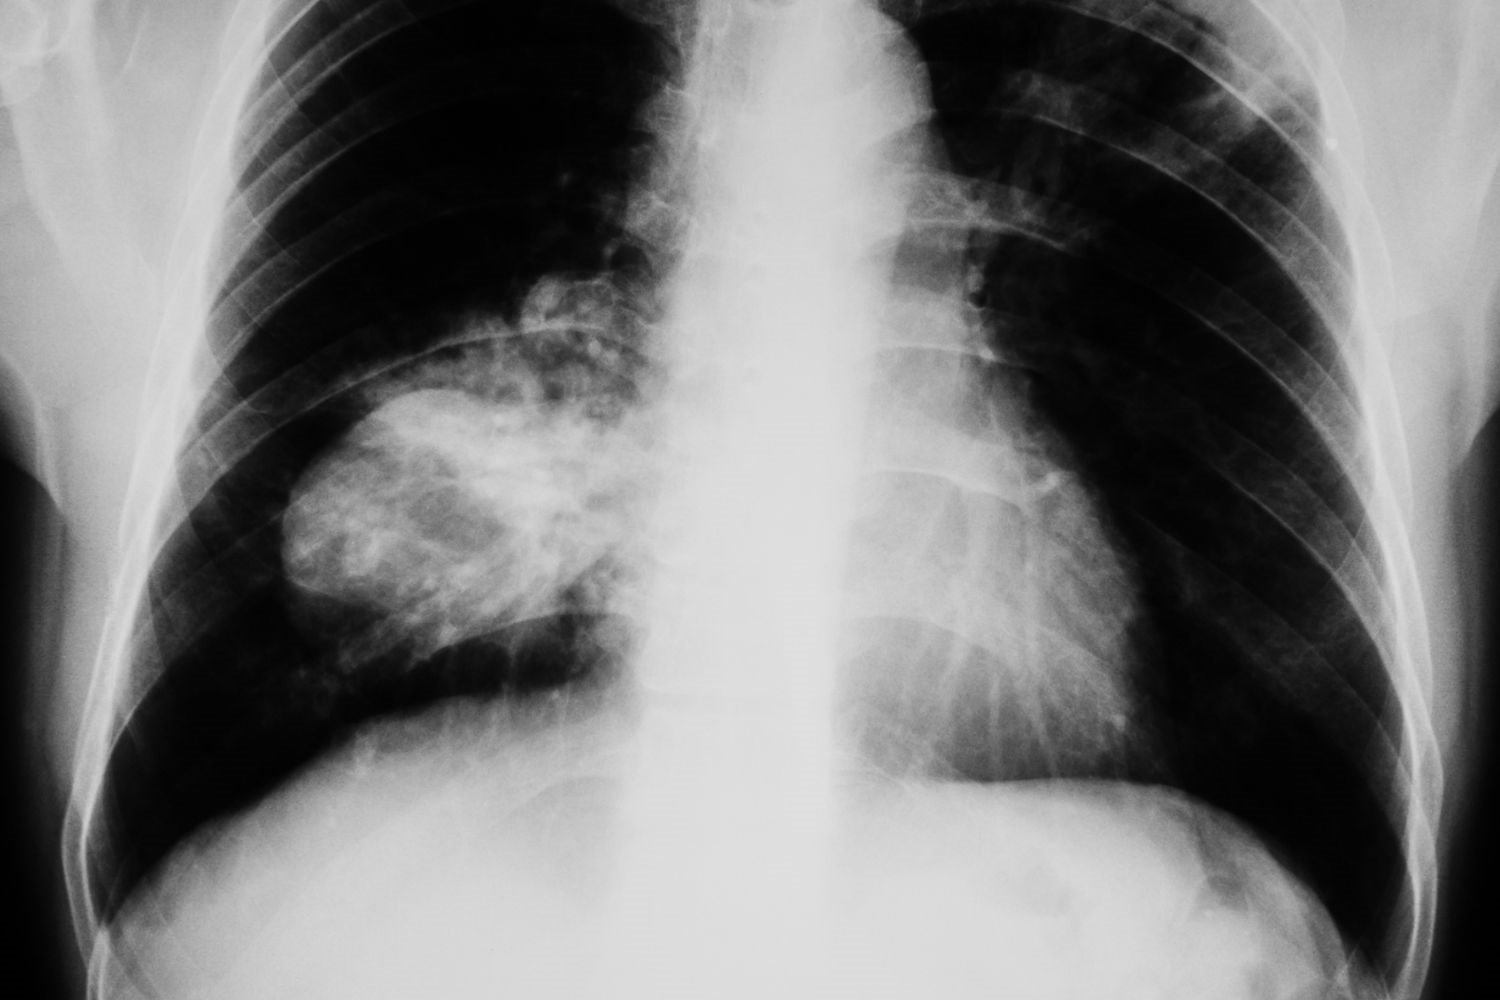

La Asociación para la Investigación del Cáncer de Pulmón en Mujeres reclama mejorar la detección precoz

La atención al cáncer de pulmón de célula pequeña (CPCP) en mujeres es un reto global de primer orden, al tratarse de unas de las formas más agresivas de cáncer de pulmón, que afecta al 15% de los diagnósticos y registra una creciente incidencia en mujeres en los últimos años.